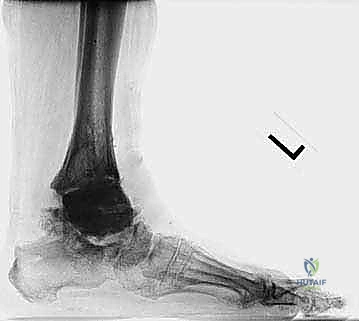

FIG 1 • Acute ( A ) and chronic ( B ) medial malleolus fractures. The former fractures occur due to an intraoperative technical error.

FIG 1 • Acute ( A ) and chronic ( B ) medial malleolus fractures. The latter can occur from imbalance about the prosthesis with undue stresses.

The natural history of malleolar fractures is compromised by the limited bone available due to the prior implant. This reduces the surface area for healing, increasing the likelihood of nonunion. Nonunion can lead to a relative increase in malleolar length and subsequent ligamentous laxity, predisposing to instability and deformity. Once deformity is present, it creates abnormal stresses that further hinder union.